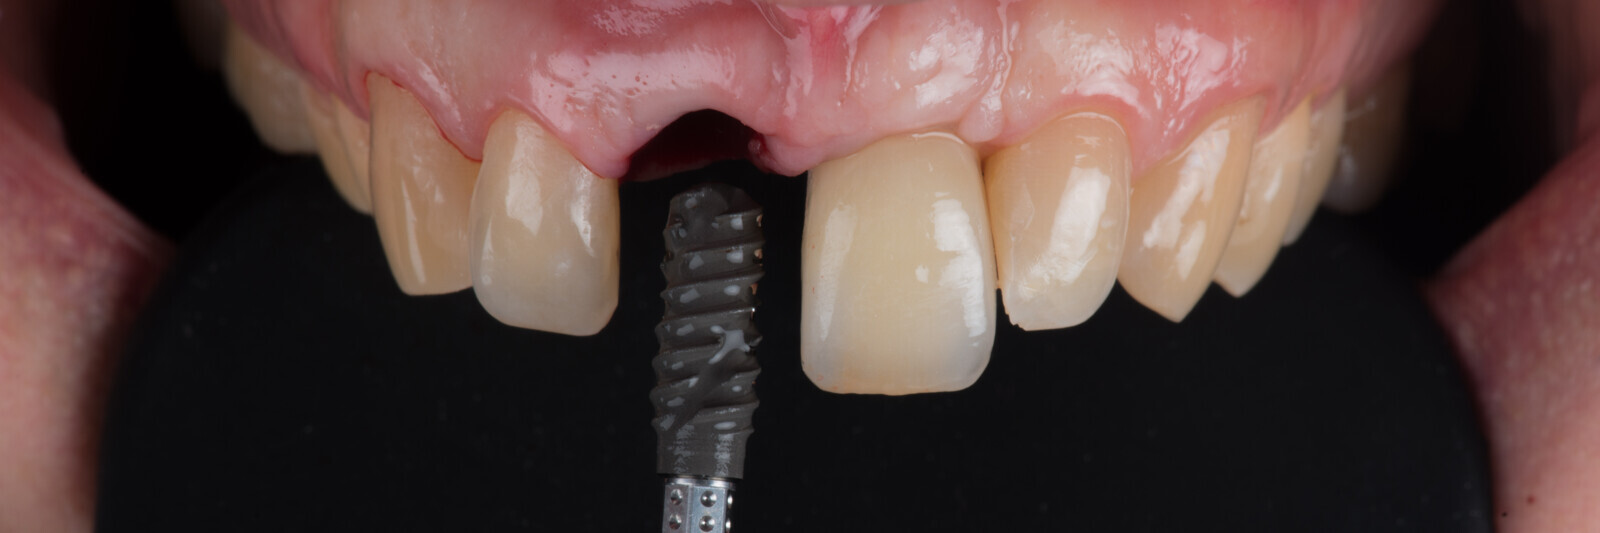

Immediate placement and restoration of a Straumann BLX implant replacing maxillary incisors